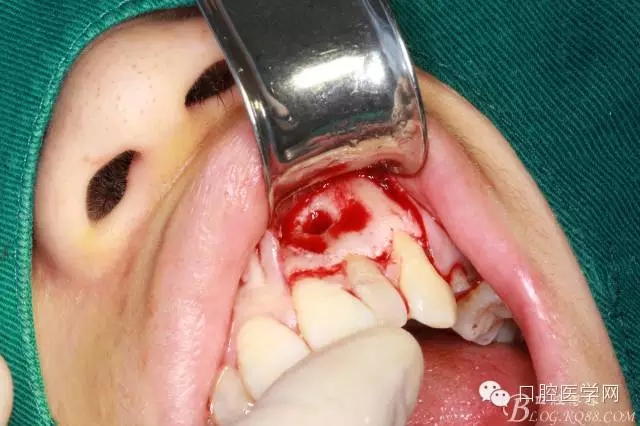

翻全厚瓣(-)

翻全厚瓣(二)

翻全厚瓣后暴露骨面

確定根長(根管充填時已確定)

去 骨